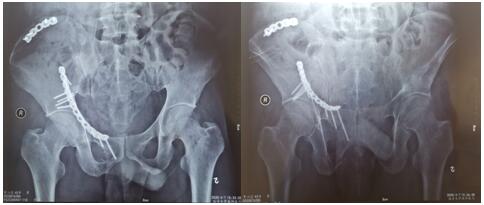

术后影像学资料如下:

骨盆骨折多由高能量损伤所致,多伴有合并症或多发伤,处理棘手,致残率高达50%~60%。经过孟泽祖主治医师、李鹏鹏住院医师的精心管理与辛勤付出,患者曹某腰椎骨折术后病情恢复良好。于2020年4月1日在全麻下行骨盆粉碎性骨折切开复位内固定术,患者多处骨盆粉碎性骨折,病情复杂,手术时间长,术中出血多。首次采用改良stoppa+右髂后上棘联合入路,手术顺利,术后病情不稳定,经过主管医师孟泽祖与全科骨干医师、护士的通力合作与坚守,术后病情日趋稳定。复查下肢血管超声提示:未见明显血栓。患者曹某在我院经过标准化、专业化的综合治疗后,患者病情恢复良好,神经损伤症状已基本恢复,伤口I级愈合,患者带着满意的笑容康复出院了。